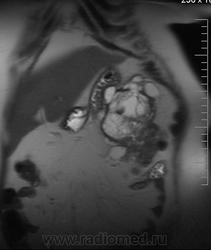

очень характерная картина для метастаза рака яичника, к сожалению.

Не могу достоверно определить локализацию метастаза брюшной полости, вероятно в лимф. узел с инвазией оободочной кишки. Рецидив С-r левого яичника думаю, что с инфильтацией левой стенки прямой кишки и культи влагалища, вторичная лимфаденопатия л/у малого таза. каликопиелоуретероэктазия (инвазия нижних отделов левого мочеточника?) Холедох широковат, но желтухи по внешнему виду нет.

Прорастание левого мочеточника рецидивной опухолью есть 100%, метастаз в большой сальник характерен для рака яичников, как и сигнальные характеристики его. Культя в данном случае шейки матки.